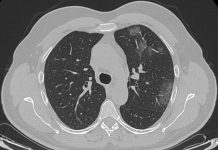

Si esegue d’urgenza, a completamento diagnostico, indagine TC del Torace in condizioni basali ed algoritmo ad alta risoluzione (HRCT), con scanner a 64 strati, le cui immagini ottenute sono state analizzate con slice-thickness di 1,2 mm e successive ricostruzioni MPR (assiali, sagittali e coronali).

HRCT ha documentato, in entrambi i parenchimi polmonari, la presenza di plurimi addensamenti con aspetto “a vetro smerigliato” ed alcune aree con pattern “crazy-paving”, per la coesistenza di aree “ground-glass”, di consolidamento ed ispessimento interstiziali. Trachea e bronchi pervi. Qualche piccolo linfonodo, reattivo, in sede ilo-mediastinica. Immagine cardiaca nei limiti. Non evidenza di versamento pericardico. Minimo versamento pleurico basale bilaterale.

La TC ha messo bene in evidenza, inoltre, il “segno ragnatela” (“spider web sign”), rappresentato da un’area di opacità ground-glass, ad aspetto grossolanamente triangolare ed angolare, in sede basale sub-pleurica a destra, con all’interno setti interlobulari ispessiti come una rete; la pleura adiacente era stirata ed ispessita, denotando una forma simile a quella di una ragnatela nell’angolo.